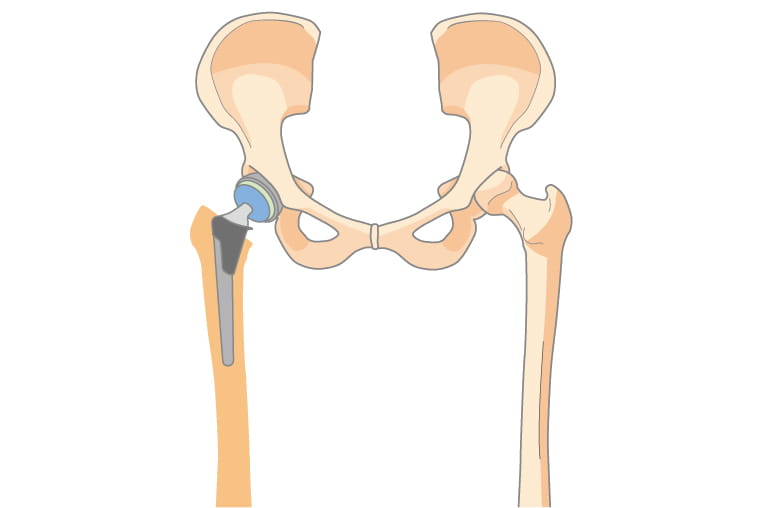

人工股関節置換術(THA)とは

変形性股関節症や大腿骨頭壊死症、関節リウマチの股関節病変など様々な疾患のために股関節に著しい障害が起こり、痛みや動きづらさで日常生活に支障が出てくる場合があります。そのような場合に、その障害のある関節を金属やセラミック、ポリエチレンなどでできた人工関節に入れ替えることで、痛みがなくなり、歩行能力が改善されます。